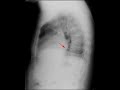

This is a 42 year old woman who presented with shortness of breath and pain in her fingers. Frontal and lateral radiographs of the chest were obtained. The red arrow on the frontal radiograph corresponds to a column of air within a dilated esophagus. The green area corresponds to interstitial thickening at the right lung base. The lateral radiograph nicely demonstrates air within a dilated esophagus. The red arrow points to dilation of the gastroesophageal junction. A dilated esophagus can be seen with many entities including achalasia, pseudoachalasia, and esophageal strictures. However, given the interstitial changes in the lower lobes as well as the clinical history of finger pain, the findings are most consistent with scleroderma. Scleroderma affects the smooth musle of the esophagus leading to dilatation and deficiency of the gastroesophageal junction. Patients with scleroderma not uncommonly develop interstitial lung disease.